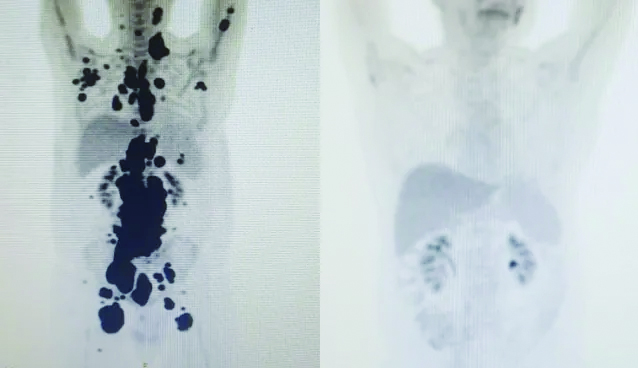

Paulo Peregrino lutava contra o câncer há 13 anos e estava prestes a receber o tratamento por meio dos cuidados paliativos quando, em abril deste ano, foi submetido a um tratamento considerado revolucionário no combate à doença e, em apenas um mês, teve remissão completa do seu linfoma.

O publicitário, 61 anos, é o caso mais recente de remissão completa em curto período de tempo do grupo de estudos do Centro de Terapia Celular. O protocolo foi adotado pela USP, em parceria com o Instituto Butantan e o Hemocentro de Ribeirão Preto.

Paulo teve alta no último domingo (28), depois de ficar sob cuidados médicos no Hospital das Clínicas, da cidade de São Paulo. “A vitória não é só minha. É da fé, da ciência e da energia positiva das pessoas. Cada uma delas ajudou a colocar um paralelepípedo nesse caminho. A imagem prova com muita clareza, para qualquer pessoa, a gravidade do meu linfoma, e eu não tinha ideia de que era assim. Tenho certeza de que, pelo menos, terei, modestamente, passado esperança a quem tanto precisa.

Só quero que as informações e o conhecimento adquiridos com meu caso possam servir a outros pacientes no futuro”, declarou, nas redes sociais